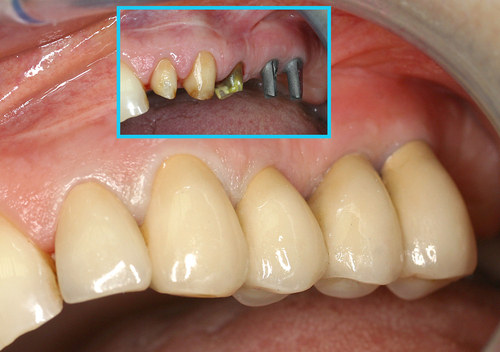

L’état initial (fig.26) montre une péri implantite généralisée au maxillaire et à la mandibule.

Fig. 26

Infection généralisée des implants dentaires